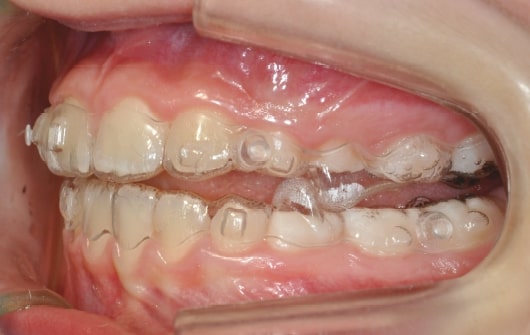

Malocclusion A6 Correction of Mandibular Retrusion in Growth phase patient | Skeletal Class II | Class II Division 1 malocclusion | Deep bite | Mixed dentition

Initial Photos and datas

Clinical examination and diagnosis

DENTAL:

- Molar and Canine class 2 on the right side – Molar and Canine clss 1 on the left side

- Upper diastema (11-21)

- Increased Overjet

- DeepBite

- Reduced Transversal Diameters

- Deviated Lower Midline 2 mm to the Right